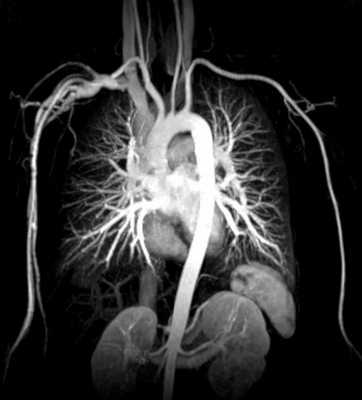

МРТ брюшной аорты

Компьютерная томография (КТ) и магнитно-резонансная томография (МРТ) - это два принципиально разных диагностических метода. Метод КТ основан на измерении и сложной компьютерной обработке разности ослабления рентгеновского излучения различными по плотности тканями. При магнитно-резонансной томографии используют не радиоактивное излучение, а эффект магнитного поля и ядерного резонанса. Поэтому проходить МРТ обследование брюшной аорты можно неограниченное количество раз с любым временным интервалом. Оно также безопасно, как и УЗИ. Полученные как при МРТ, так и при КТ брюшной аорты снимки имеют высокое разрешение и могут стать основой для построения 3D модели сосудистого русла, что расширяет возможности по его обследованию.

По сравнению с компьютерной томографией МРТ брюшной аорты создает более четкие и детальные снимки мягких тканей и опухолевых поражений, на которых хорошо просматриваются мельчайшие кровеносные сосуды ветвей. КТ будет предпочтительным методом исследования для выявления аневризмы аорты, ее типа и степени угрозы здоровью пациента. КТ брюшной аорты с внутривенным контрастированием позволяет хорошо визуализировать аневризму аорты, очень точно оценить её размеры, обнаружить расслоение стенки. Однако компьютерная томография не всегда дает точные сведения о вовлечении в процесс ветвей аорты, сопутствующих окклюзионных и стенотических поражениях артерий.

КТ аорты в обязательном порядке делается с применением контрастного вещества на базе йода. Это существенным образом увеличивает стоимость томографии. МРТ аорты во многих случаях не требует контрастирования, поскольку кровь сама является хорошим парамагнетиком в магнитном поле томографа. Это делает магнитно-резонансную томографию более дешевым и безопасным обследованием сосудистой системы.